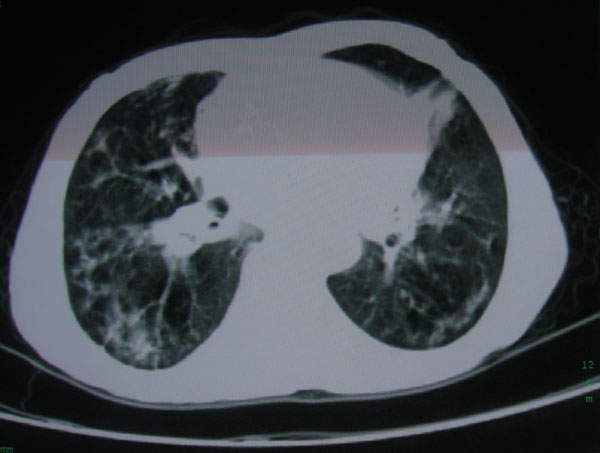

标题: CT15046:F59Y,咳嗽间断咳血丝痰就诊. [打印本页]

咳嗽\间断咳血丝痰就诊.

慢性支气管炎伴支气管扩张\\感染

肺间质性改变 支气管扩张合并感染

慢性支气管炎伴全小型肺气肿、支气管扩张、感染、间质纤维化。

慢性支气管炎伴支气管扩张、感染,间质纤维化。

慢性支气管炎伴全小叶型肺气肿、支气管扩张、感染、间质纤维化